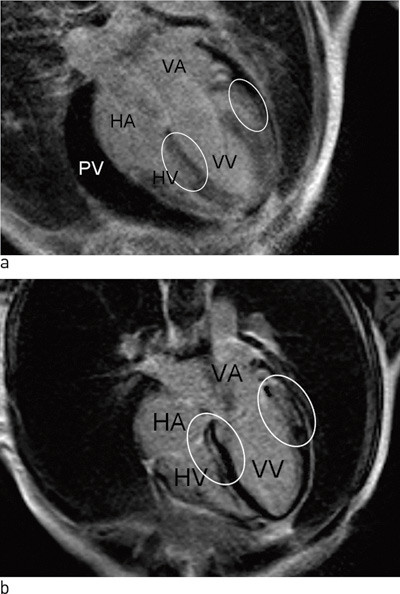

Akutt myokarditt er en betennelse i hjertets muskelvev, som oftest forårsaket av infeksjon. Utbredelsen kan variere fra fokal til generalisert med affeksjon av hele myokard i fulminante tilfeller (fig 1). Den kliniske presentasjonen er variabel og reflekterer til en stor grad omfanget av myokardial affeksjon. Akutt myokarditt har ofte et subklinisk og selvbegrensende forløp, men kan også debutere med hjertesvikt, dilatert kardiomyopati, livstruende arytmier eller plutselig død (1) – (3).

Det foreligger derfor et behov for en ikke-invasiv diagnostisk metode for å diagnostisere myokarditt og for å vurdere prognosen og effektiviteten av behandlingen. Hjerte-MR med kontrast er godt egnet til å diagnostisere myokardskade forårsaket av både akutt og kronisk myokarditt (8). Myokardskaden ved myokarditter har en karakteristisk epikardial utbredelse og følger ikke forsyningsområdet til koronararterier. Dette er i motsetning til myokardinfarkter, som alltid har en dominerende subendokardial utbredelse. Områder med kontrastopptak ved hjerte-MR korrelerer godt med aktiv myokarditt ved histopatologisk undersøkelse (6). I tillegg gir MR av hjertet informasjon om hjerte- og perikardfunksjon.

Kontrastbasert MR vil kunne avdekke uoppdaget gjennomgått myokardinfarkt, slik som vi fant hos en av pasientene som hadde angiografisk normale koronararterier. Ved myokardinfarkt på grunn av en okkludert koronararterie vil alltid kontrastoppladningen følge distribusjonsområdet til koronararterien og være subendokardial med varierende grad av transmuralitet (fig 2). Ved myokarditt vil kontrastoppladningen være epikardial og ikke følge koronararteriens forsyningsområde (fig 3). Det kan oppstå vansker med diagnostisering av myokardskade på grunn av myokarditt i forhold til myokardskade på grunn av myokardinfarkt dersom det samme området av myokard er rammet.